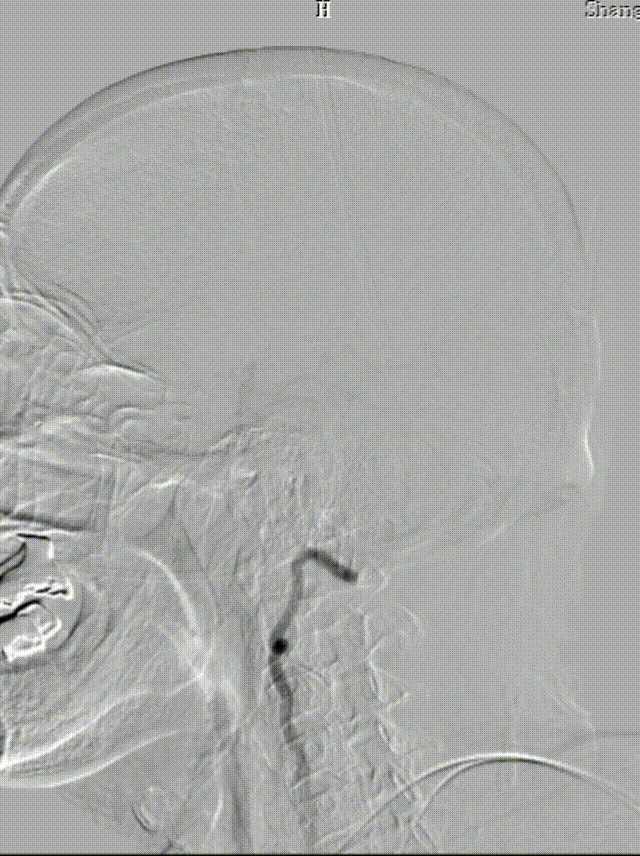

患者出现意识模糊、呕吐、胸闷等不适,查体:血压升高(血压200/100mmHg),神清,对答切题,伸舌居中,查体部分配合,四肢肌力5级,双眼向右凝视伴水平眼震。

立即行Dyna-CT,未见脑出血表现,立即予以尼卡地平及尼莫地平降压,动脉静推负荷量替罗非班。

双侧锁骨下动脉造影见椎动脉、基底动脉血流通畅,远端未见栓塞表现。

术后头晕呕吐,当日DWI:左侧小脑梗死,MRA未见明显大血管栓塞。

术后第3天患者恶心、呕吐症状消失,仍有头晕,复查DWI及MRA。

术后第5天,头晕症状完全消失,双上肢收缩压差8mmHg,NIHSS 0分。